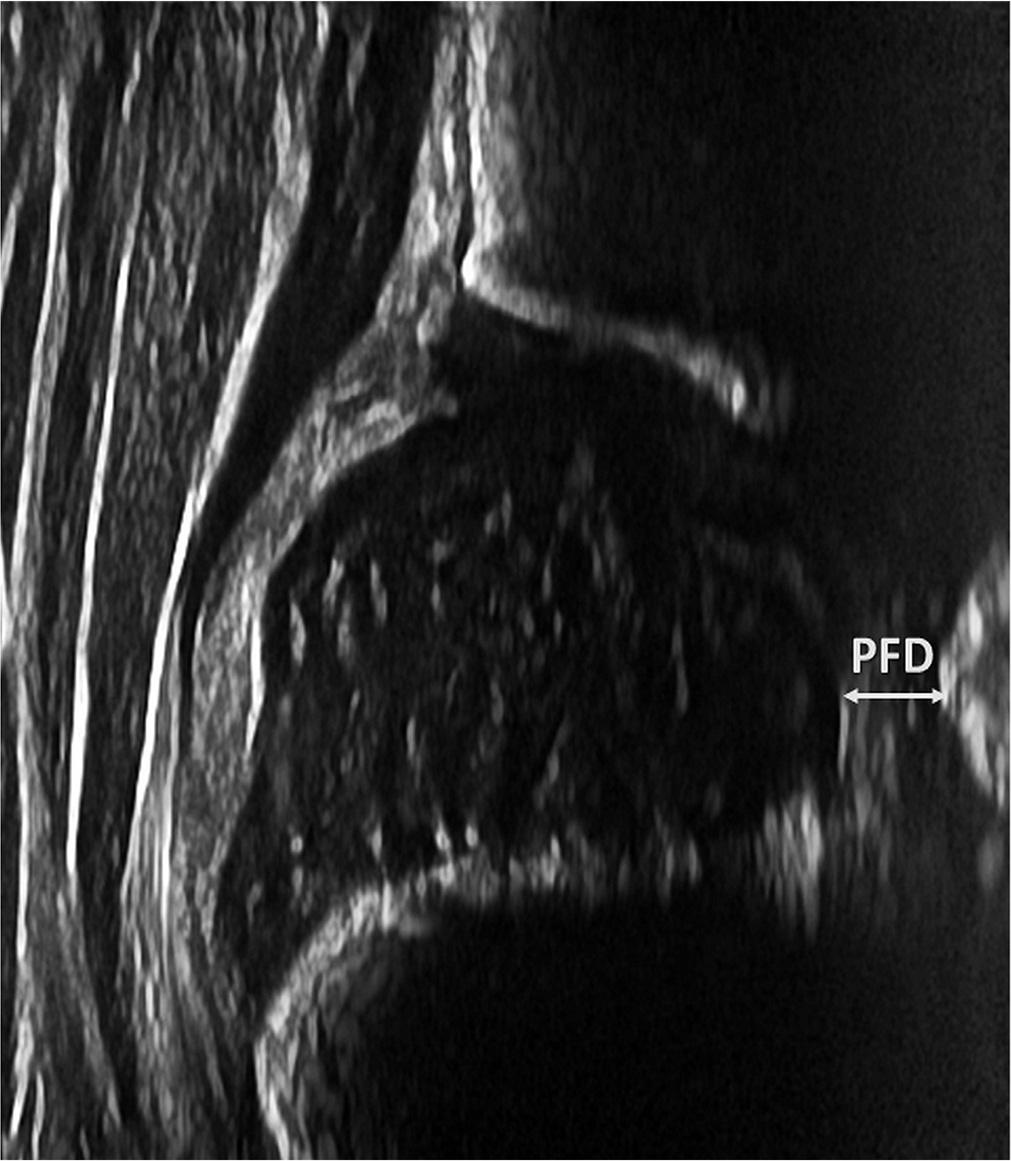

Measurements of the PFD were performed with a slight probe movement, anterior in relation to the “standard plane”(7), to visualize the pubis (Fig. 2).

Measurement of the pubofemoral distance (PFD)

It should be emphasized that all our measurements were performed on the “standard plane”, as defined by Graf(7). “Out-of-plane” measurements were only used for the measurement of PFD, the performance of which, in our study, was poor: with a cut-off value of 2.88 mm, sensitivity was 52% and specificity was 68%. Consequently, the utility of PFD to differentiate between type I and type II hips is very limited and not recommended.